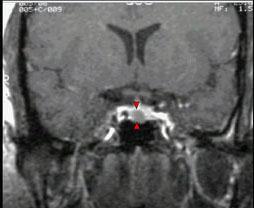

女,38岁,头痛、闭经,MRI检查如图,选择最可能的诊断()A.垂体囊肿B.垂体梗死C.转移瘤D.垂体微腺瘤E.垂体脓肿

问题 女,38岁,头痛、闭经,MRI检查如图,选择最可能的诊断()

选项 A.垂体囊肿 B.垂体梗死 C.转移瘤 D.垂体微腺瘤 E.垂体脓肿

答案 D